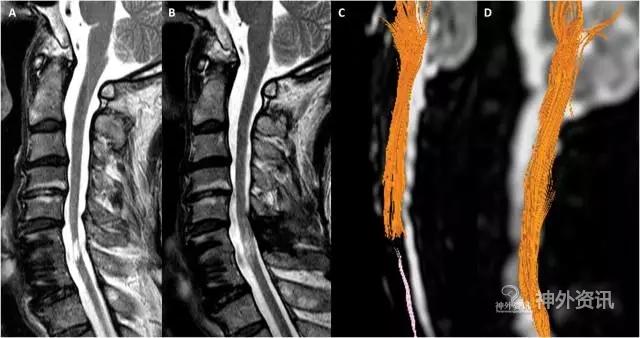

16例患者完成该项研究,包括15例男性和1例女性;平均年龄40.9岁。神经功能方面,仅2例肢体活动获得明显改善;其中1例右上肢C8段支配区肌力由1级提升至3级;1例双上肢C6段支配区肌力由3级提升至4级,右上肢C8段支配区肌力由0级提升至1级。该2例也是唯一在MRI-DTI上出现新生纤维束的患者(图3)。4例患者SEP检查表现显著改善,6例MEP检查表现一定程度改善。术后随访过程中,均未出现脑脊液漏、中枢神经系统感染及二次手术等严重并发症。8例患者出现轻度的不良反应,包括部分肌群僵硬、感觉减退和疼痛等,经保守治疗后均获得好转。

图3. 1例症状获得改善的患者,术前术后MRI检查结果。A. 术前MRI显示,C6-7节段创伤性空腔形成;B. 术后6月示脊髓增粗,空腔边缘模糊;C. 术前DTI显示,纤维束走行状况;D. 术后DTI显示,新生纤维束形成。